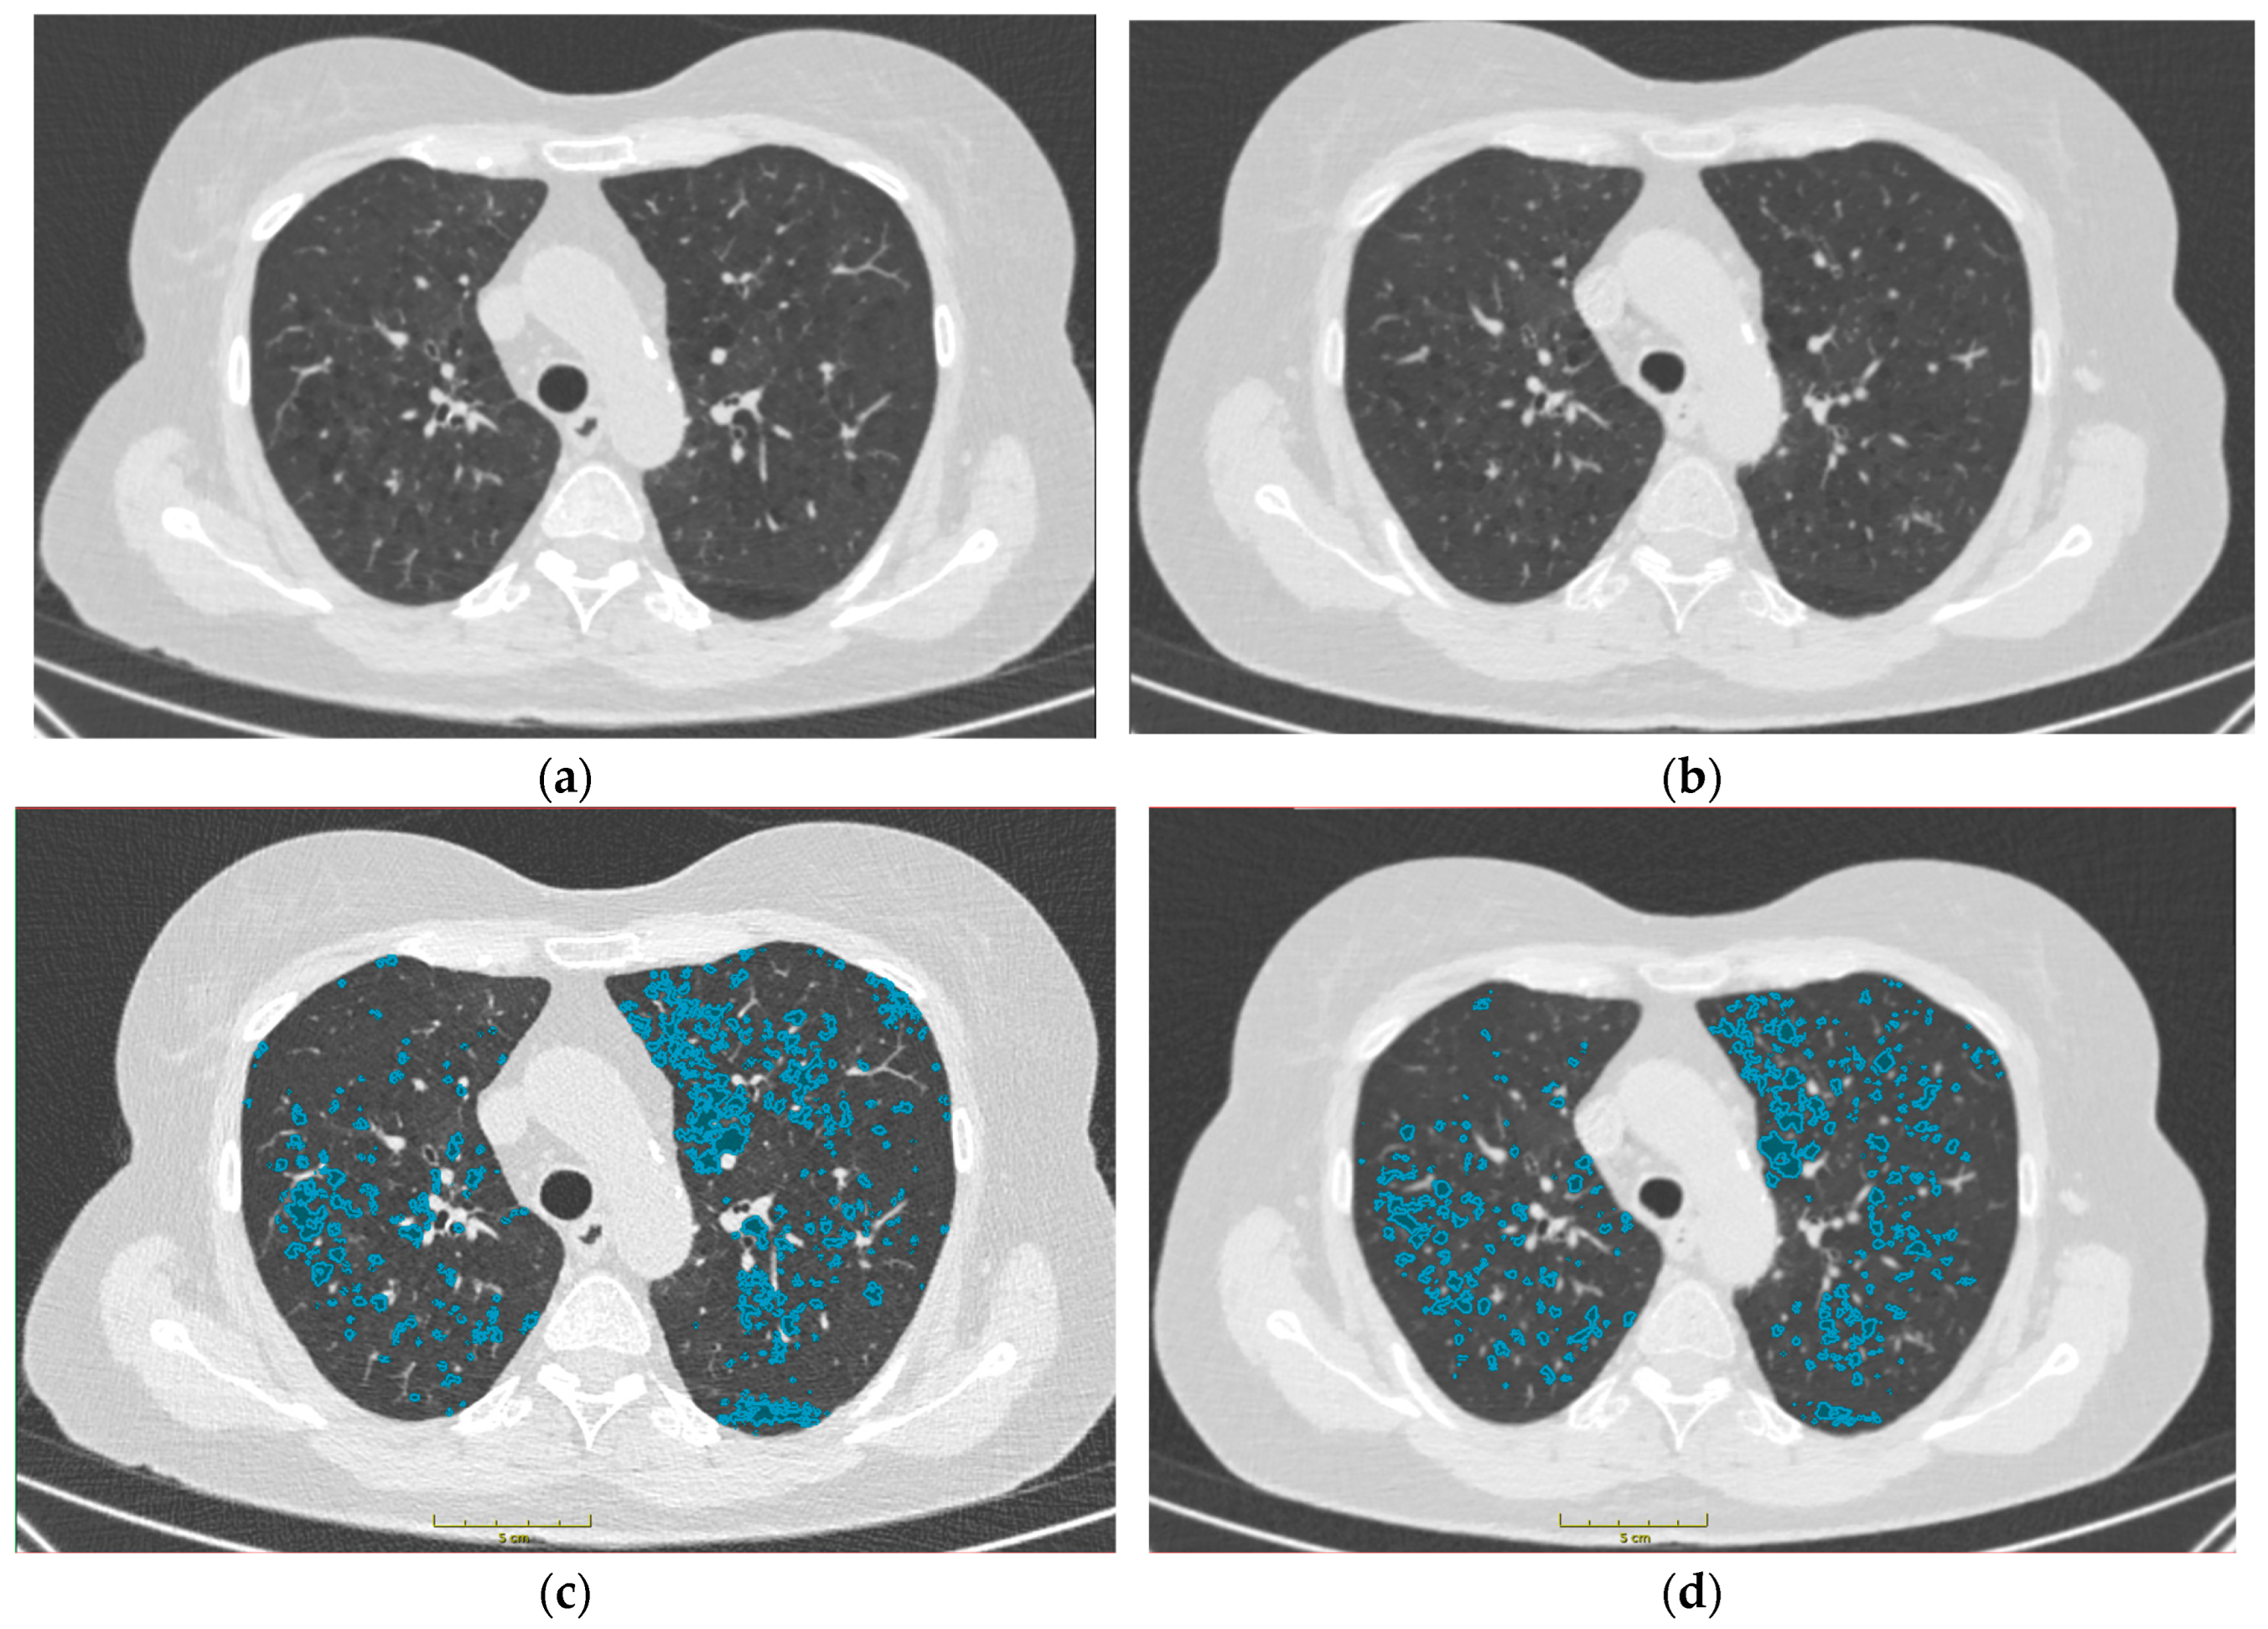

3.1. Comparison of Emphysema in TNC and VNC Images

3.2. Comparison of Pre-Emphysema in TNC and VNC Images